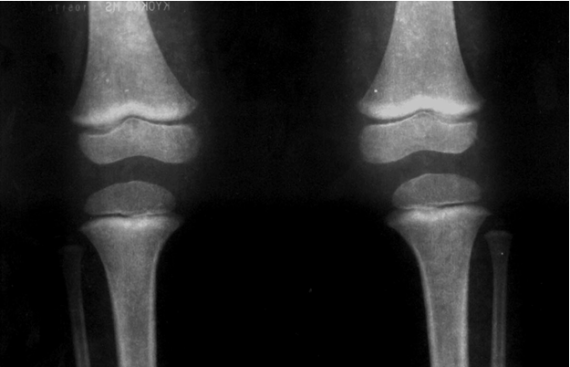

Los estudios que miden los niveles de plomo en la tibia (hueso de la espinilla) con una prueba no invasiva llamada fluorescencia de rayos X han encontrado que los aumentos en la presión arterial están asociados con niveles más altos de plomo en los huesos.